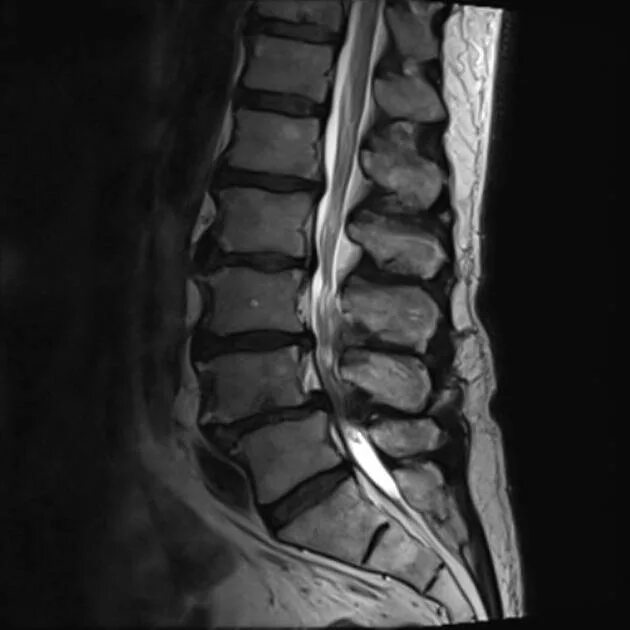

Как лечить стеноз шеи